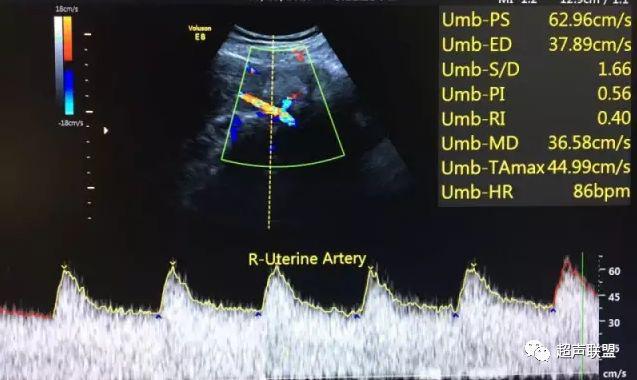

图1 正常脐动脉血流频谱

图2 脐动脉舒张期血流消失或反向

1 胎儿脐动脉测定

缺氧首先出现的变化是舒张末期血流降低,S/D值、RI值和PI值升高。当缺氧进入再分配晚期时,可逐渐出现舒张期血流减少、舒张期血流缺失。失代偿期出现脐动脉血液逆流,舒张期血流倒置。

2、脐动脉标准:孕30周后,S/D>3;晚孕期,RI >0.75;孕18~20周后,脐动脉舒张期缺如或反向(后者见于严重的宫内缺氧者);